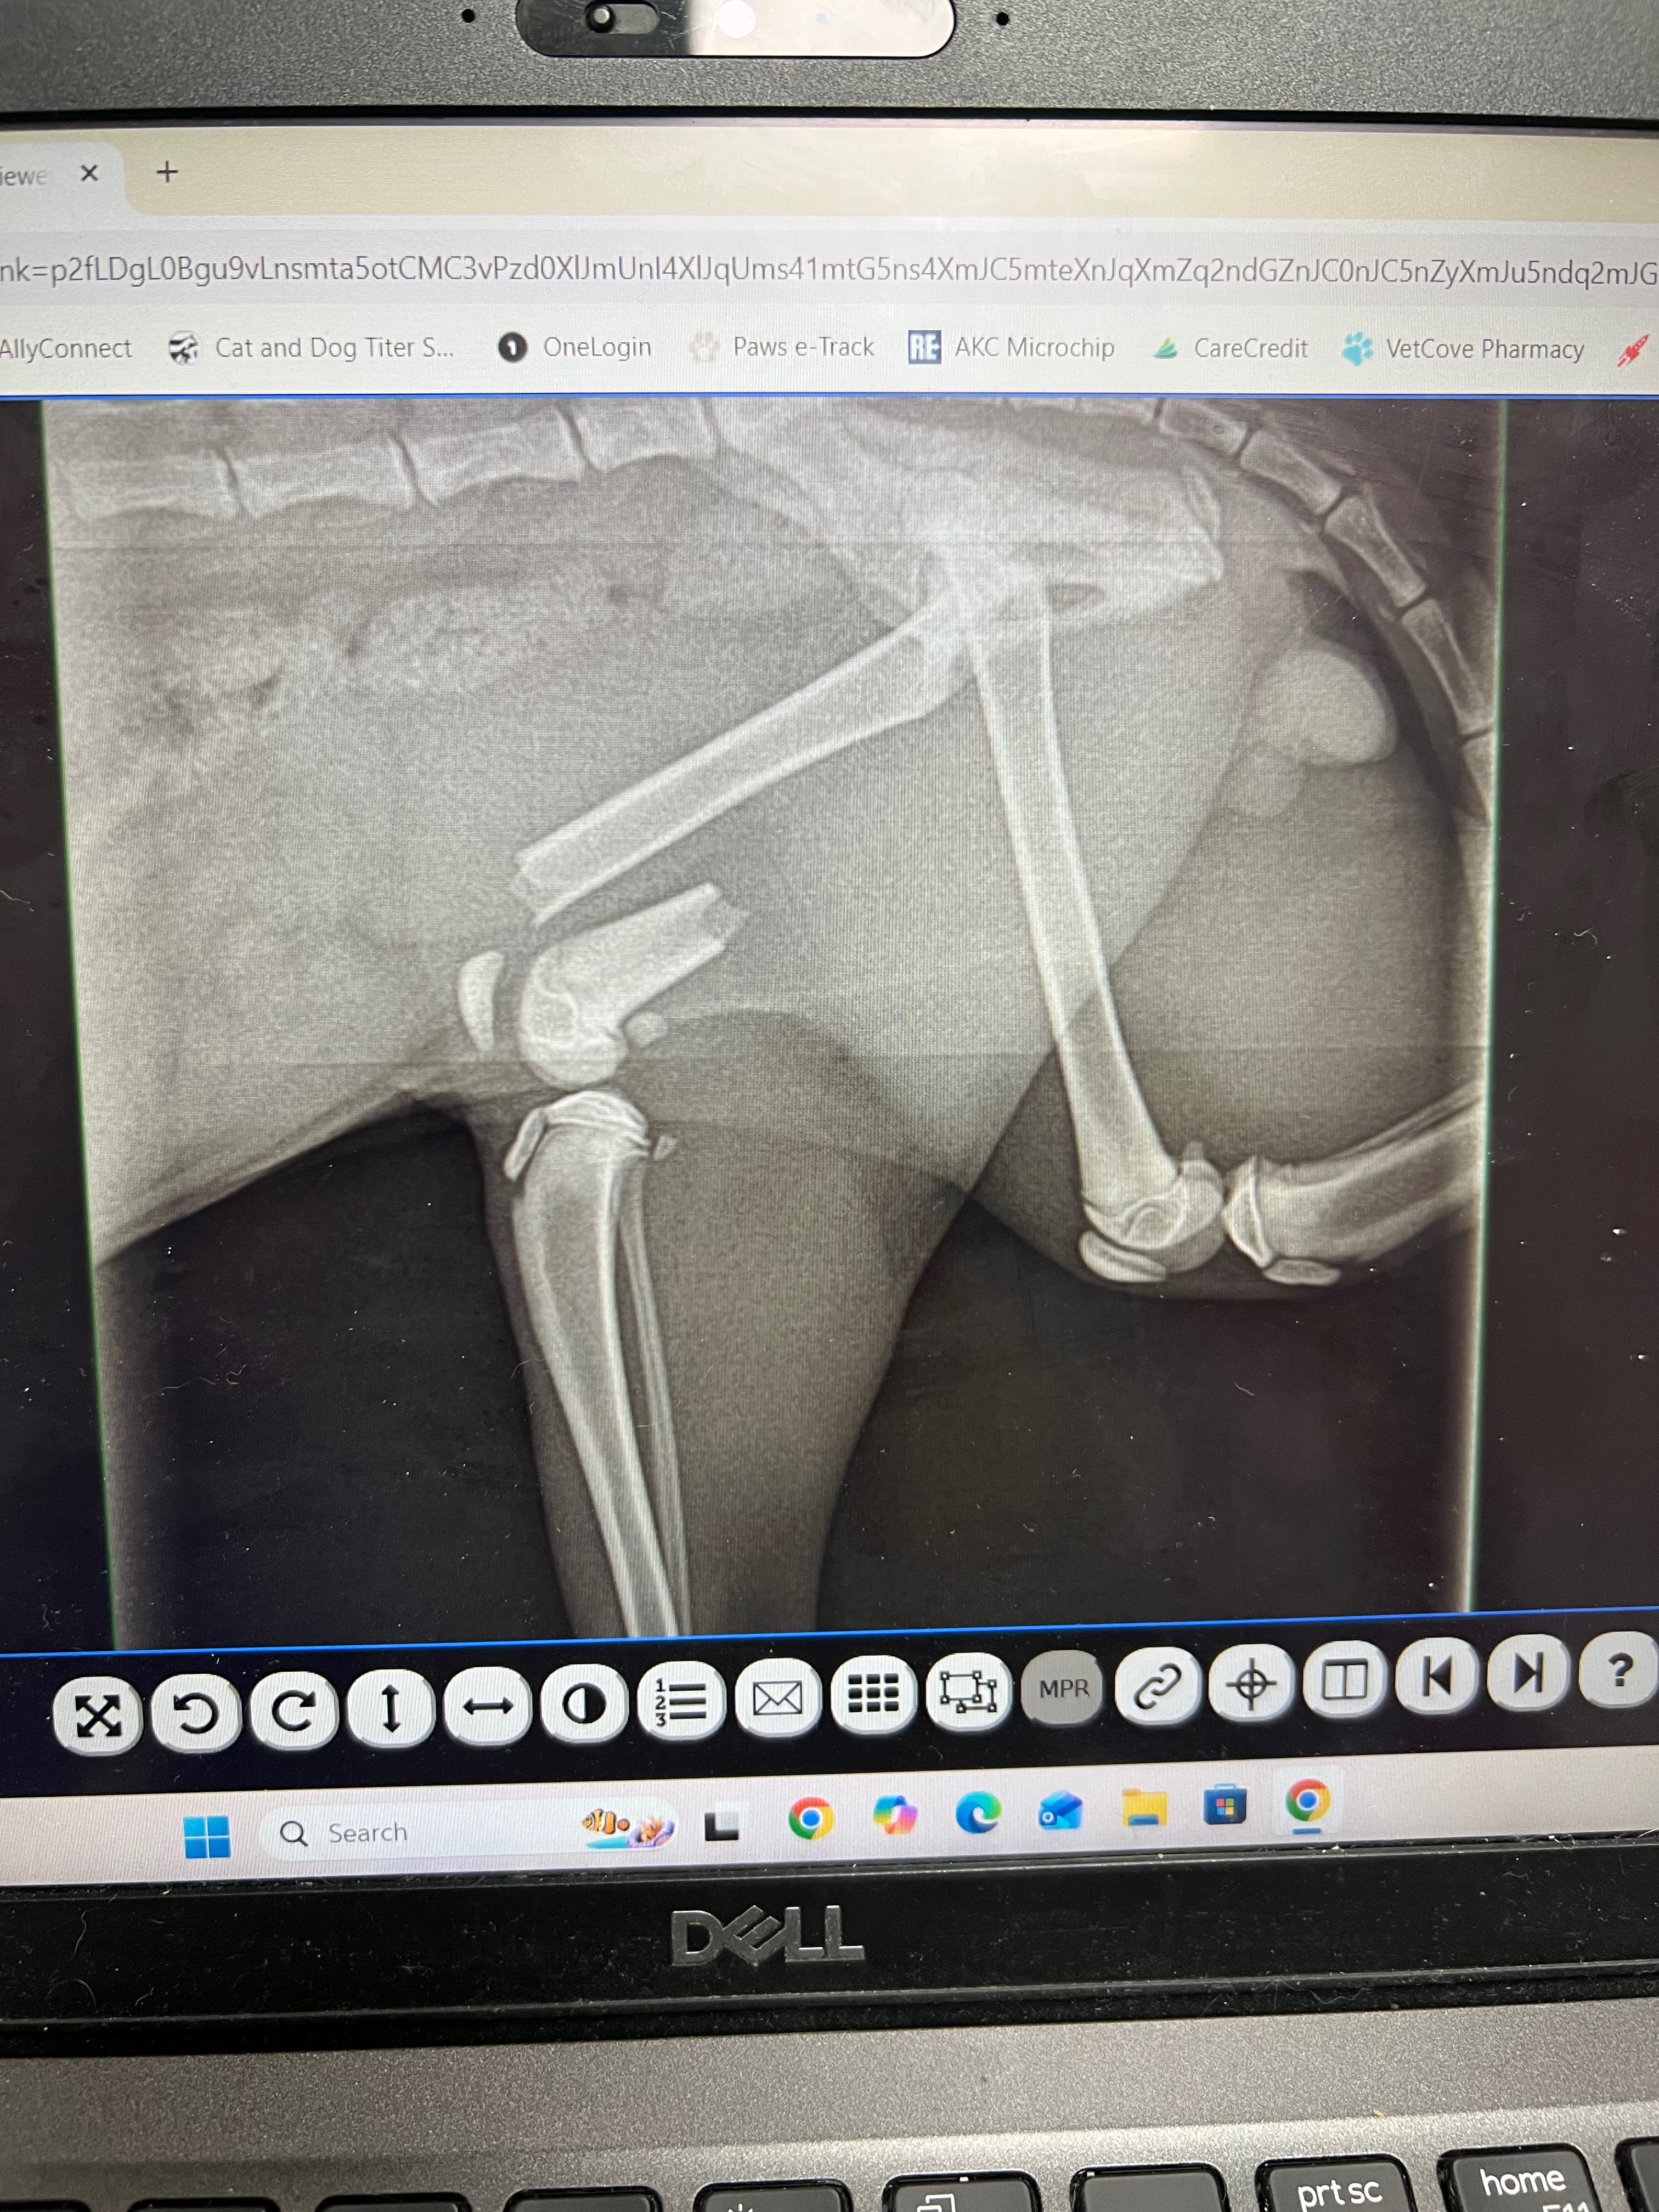

As we’re grieving this loss, we’re also facing another incredibly difficult situation. Our other cat, Tiny, has suffered a broken leg and urgently needs surgery. Watching one of our babies in pain while mourning the other has been overwhelming, both emotionally and financially.

We’re asking for help during this incredibly difficult time. Any support—no matter how small—would go toward covering emergency vet bills and giving Tiny the surgery he needs to heal and have a chance at a full life.